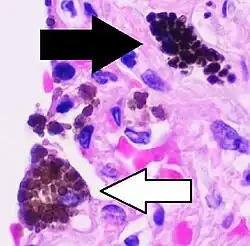

Pigmented macrophages can be classified by the pigment type, such as for alveolar macrophages shown above (white arrows). A "siderophage" contains hemosiderin (also shown by black arrow in left image), while anthracotic macrophages result from coal dust inhalation (and also long-term air pollution).[54] H&E stain.